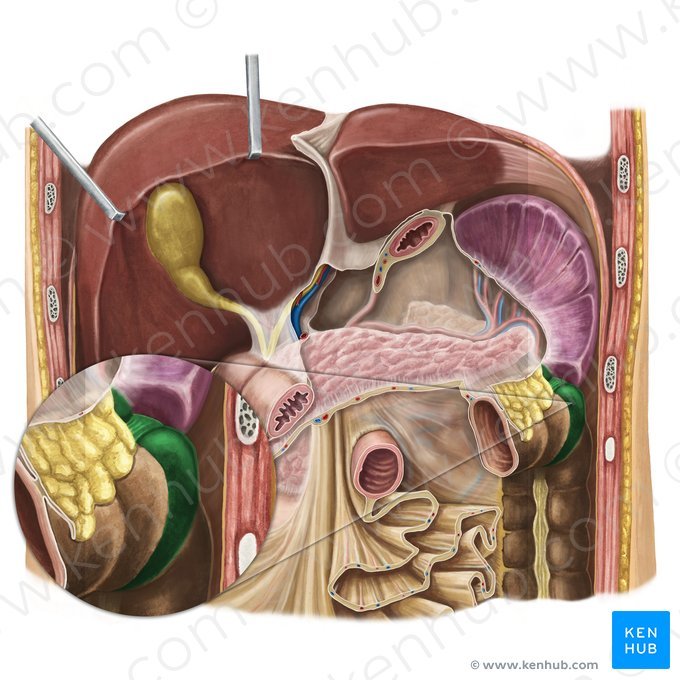

Liver

a large organ located in the upper right abdomen that produces bile, detoxifies blood, and performs many other metabolic functions.

Considered as the largest gland in the body

Pancreas

a gland located behind the stomach that produces digestive enzymes and hormones like insulin and glucagon.

Pancreas

A gland located behind the stomach that produces digestive enzymes and hormones like insulin and glucagon.

Pancreatic Duct

A duct that carries digestive enzymes produced by the pancreas to the duodenum. It typically joins with the bile duct before entering the duodenum.

Bile duct

A duct that carries bile produced by the liver and stored in the gallbladder to the duodenum, where it aids in the digestion of fats.

Major Duodenal Papilla

An opening in the wall of the duodenum where the common bile duct and the pancreatic duct typically enter to deliver bile and pancreatic enzymes.

Right lobe of Liver

The larger of the two main lobes of the liver, located on the right side of the abdomen.

Left lobe of the Liver

The smaller of the two main lobes of the liver, located on the left side of the abdomen.

Quadrate Lobe

A small, quadrilateral lobe of the liver located inferiorly and medially on the visceral surface, bordered by the gallbladder and the fissure for the round ligament.

Caudate Lobe

A small lobe of the liver located posteriorly on the visceral surface, near the inferior vena cava and the fissure for the ligamentum venosum.

Falciform Ligament of the Liver

A broad, thin fold of peritoneum that attaches the liver to the anterior abdominal wall and diaphragm. It also marks the division between the right and left lobes on the anterior surface.

Round Ligament of the Liver

A fibrous cord that represents the remnant of the umbilical vein of the fetus. It is located in the free edge of the falciform ligament.

Gallbladder

A small, pear-shaped organ located beneath the liver that stores and concentrates bile produced by the liver.

Right Hepatic Duct

A duct that carries bile produced by the right lobe of the liver.

Left Hepatic Duct

A duct that carries bile produced by the left lobe of the liver.

Common Hepatic Duct

The duct formed by the union of the right and left hepatic ducts, which carries bile away from the liver.

Cystic Duct

The duct that connects the gallbladder to the common hepatic duct, allowing bile to enter and exit the gallbladder.

Hepatic Artery

A branch of the celiac artery that supplies oxygenated blood to the liver.

Hepatic Portal Vein

A large vein that carries deoxygenated but nutrient-rich blood from the digestive organs (stomach, intestines, spleen, pancreas) to the liver for processing.

Inferior Vena Cava

Pancreatic Duct / Duct of Wirsung

The main duct that runs through the length of the pancreas, collecting digestive enzymes from the pancreatic cells and transporting them to the duodenum.

Accessory Pancreatic Duct / Duct of Santorini

A smaller pancreatic duct that branches off the main pancreatic duct and may also empty into the duodenum, usually superior to the major duodenal papilla.

Hepatopancreatic Ampulla / Ampulla of Vater

A dilated chamber formed by the joining of the common bile duct and the pancreatic duct before they enter the duodenum.

Sphincter of Hepatopancreatic Ampulla / Sphincter of Oddi

A muscular valve that surrounds the hepatopancreatic ampulla and controls the flow of bile and pancreatic juice into the duodenum.

Major Duodenal Papilla

The raised opening in the wall of the duodenum where the hepatopancreatic ampulla typically empties its contents.